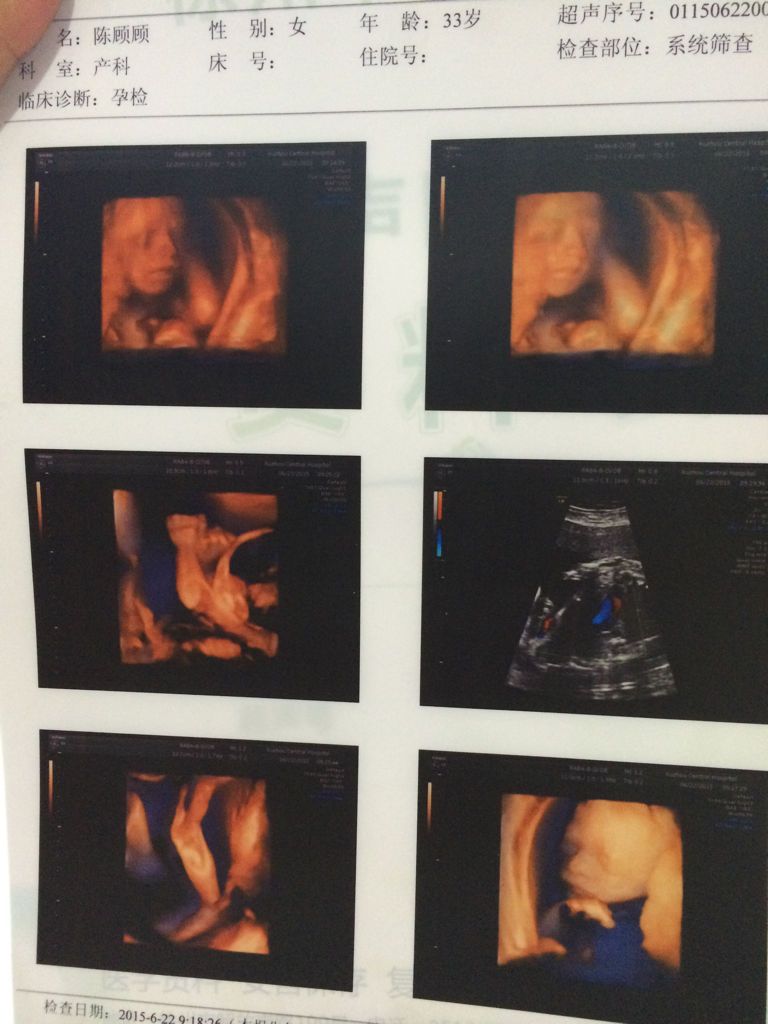

请问有懂彩超的朋友帮我看看这几张图是男宝还是女宝,真的很想知道,我不懂,我 真心的谢谢你们了,不多

请问有懂彩超的朋友帮我看看这几张图是男宝还是女宝,真的很想知道,我不懂,我 真心的谢谢你们了,不多说了,直接给分。

光贫这些看不出 男女要B超好久 翻动胎儿岩暖命姿势 全面看清胎儿 找锅眨到小鸡鸡才能确定 但不准确得 比较B超是机器 肉眼是看不清全部的 自己的总是好的 在乎男女查肿干什么